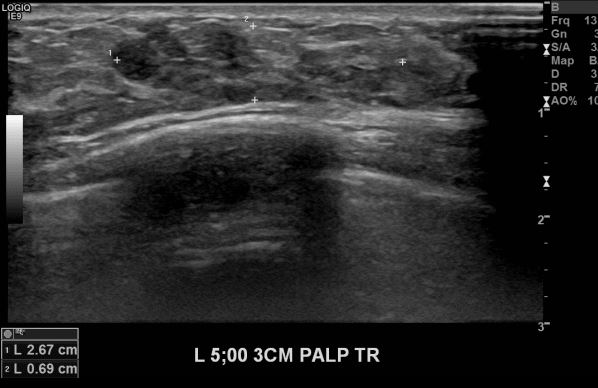

상기 환자 좌측 유방에 만져지는 멍울로 내원하여 왼쪽 5시방향 3cm 떨어진 곳 조직검사하여 제자리암 나왔습니다.